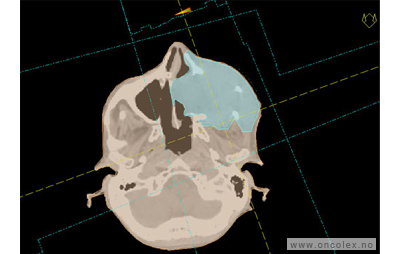

Skisse over hvordan strålefeltet planlegges:

Illustrasjon for målvolum

• GTV (Gross Tumor Volume): Identifisert tumor.

• CTV (Clinical Target Volume) GTV + omkringliggende vev hvor det kan væremikroskopisk spredning.

• ITV (Internal Target Volume): CTV + en indre margin som tar hensyn tilindre bevegelser og endringer av CTV.

• PTV (Planning Target Volume): Innstillingsmargin som inneholder ITV og samtidig tar hensyn til antatte pasientbevegelser, samt variasjoner i pasientopplegging og feltinnstillinger.

• Feltgrense. Tegnes som oftest på kroppen.

ICRU (International Commission on Radiation Units and Measurements)